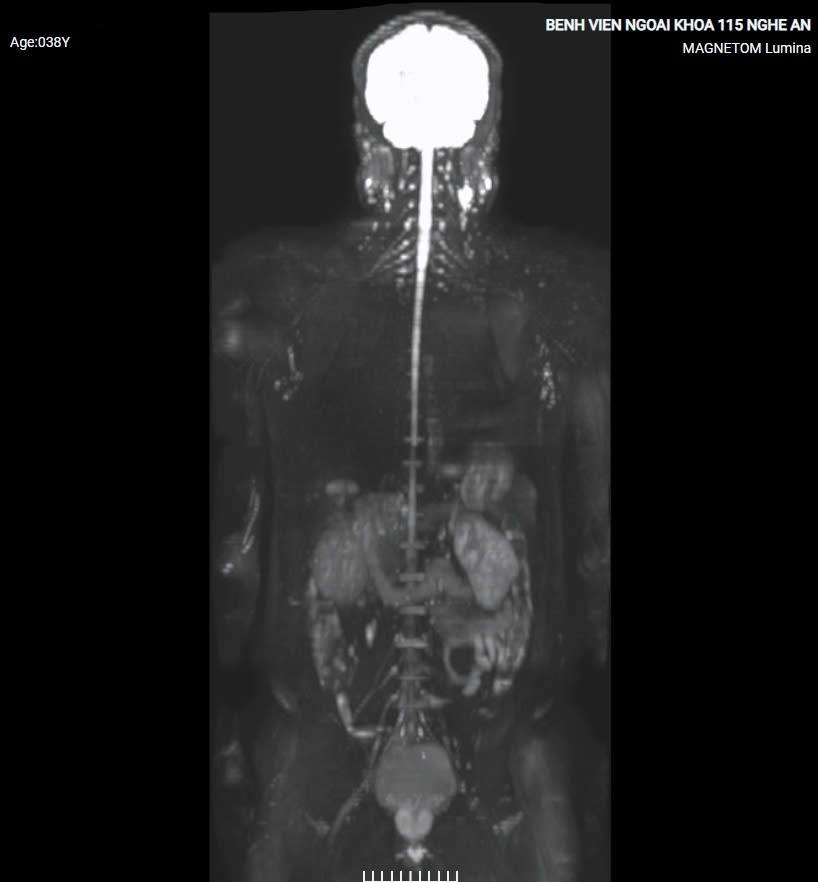

1. Chụp cộng hưởng từ toàn thân

Chụp cộng hưởng từ toàn thân là gì ?

Chụp cộng hưởng từ (MRI) toàn thân là phương pháp chẩn đoán chính xác, hiệu quả và an toàn cho người bệnh. Kỹ thuật chụp cộng hưởng từ toàn thân khảo sát các tạng trong cơ thể không sử dụng tia xạ mà thu nhận được hình ảnh chính xác bệnh lý ở sọ não, vùng cổ, lồng ngực, cột sống, gan mật, tụy, lách, tử cung – phần phụ, tuyến tiền liệt, đại trực tràng và phát hiện u ở giai đoạn sớm mới hình thành. Bên cạnh đó, khi phát hiện tổn thương trên ảnh cộng hưởng từ toàn thân chúng ta có thể chụp bổ sung thêm, khu trú vào vùng tổn thương để đánh giá rõ chi tiết tổn thương đó, cũng như mối liên quan giữa tổn thương với các cơ quan lân cận.

Khi nào cần thực hiện chụp cộng hưởng từ toàn thân?

- Khách hàng có mong muốn tầm soát phát hiện những bất thường trong cơ thể mình

- Khách hàng có tiền sử gia đình có người từng bị bệnh lý hoặc ung thư…

- Khách hàng có các yếu tố nguy cơ như: Viêm gan, xơ gan, hút thuốc lá nhiều năm, làm việc trong môi trường độc hại

- Khách hàng có triệu chứng bệnh ở cơ quan nào đó

- Kiểm tra sau khi hóa/xạ trị hoặc phẫu thuật: Thông qua kết quả chụp MRI toàn thân, bác sĩ có thể đánh giá được khả năng đáp ứng điều trị của người bệnh, đồng thời phát hiện những tổn thương tái phát/di căn nếu có